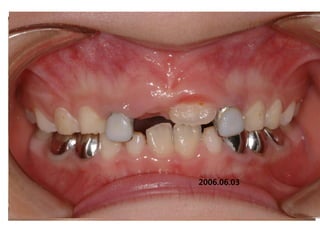

1999.05.26 /M

C.C

• Crooked teeth

Dx

• Lack of space caused by perioral muscle action

Goal

• Establish normal tongue posture and lip tone

with T4K

2006.06.03

2005.08.27